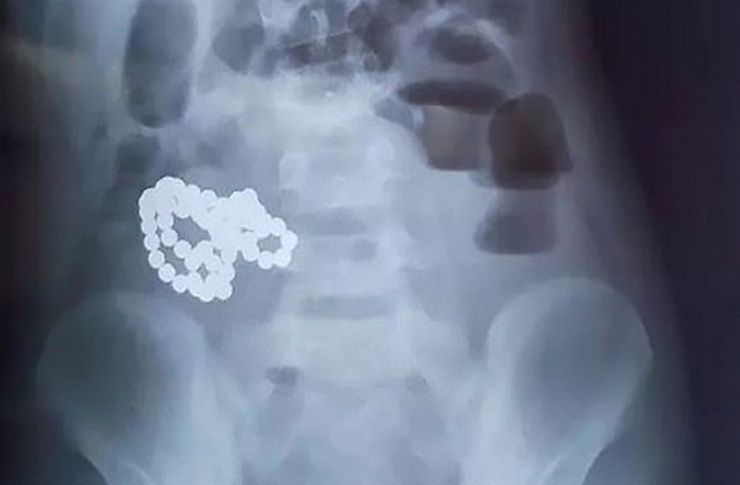

Факт кражи подтвердил рентгеновский снимок.

Факт кражи и наличие украшений у «голодного» до золота злоумышленника подтвердил рентгеновский снимок. По данному факту возбуждено уголовное дело по признакам преступления, предусмотренного частью 2 статьи 158 УК РФ (кража).